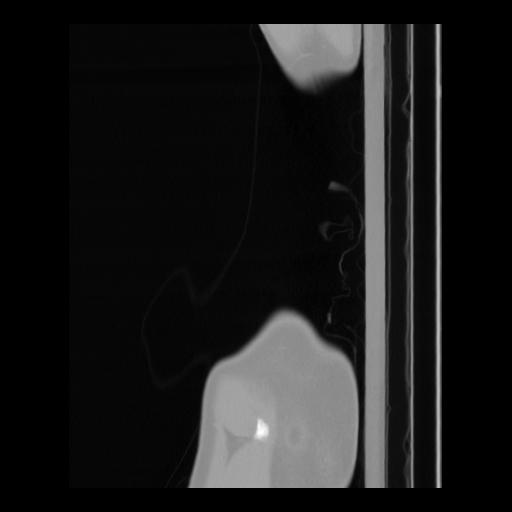

36 CUERPO,CE,Sagittal,3.000,CUERPO,Sagittal,